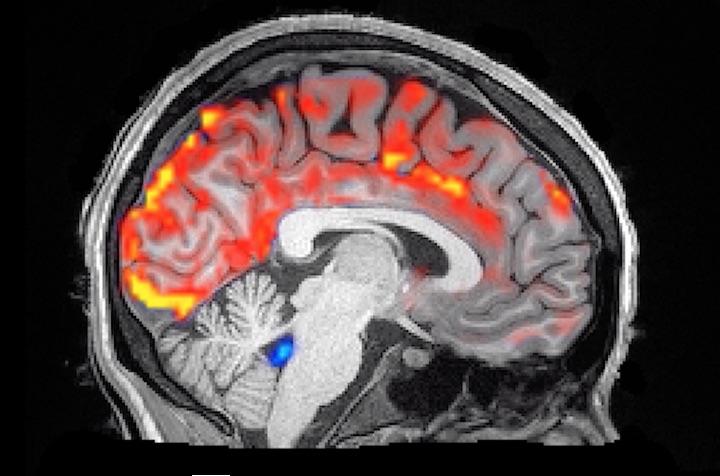

睡眠は、私たちの認知機能や脳機能のメンテナンスに不可欠なものである。このほど、ノンレム睡眠のうち、脳波に振幅の大きくゆるやかな波が多く出現し、深い眠りの状態にある「徐波睡眠」において、脳脊髄液(CSF)の流入が増え、脳内の老廃物を洗い流していることが明らかとなった。

米ボストン大学の研究チームは、高速撮像技術を用いて、ノンレム睡眠中における脳脊髄液の律動を初めてとらえ、脳脊髄液の動きと脳波の活動、血流が密接に結びついていることを示した。この研究成果は、2019年10月31日、学術雑誌「サイエンス」で公開されている。

そこで研究チームは、23歳から33歳までの成人13名を対象に、脳波(EEG)ヘッドセットで脳波を測定するとともに、MRI(磁気共鳴断層撮影装置)を用いてノン睡眠時の脳脊髄液の様子をモニタリングし、脳波において周波数の低い波が多くなると、脳の血流が低下し、脳脊髄液が脳内に流れ込むことを示した。ニューロン(神経細胞)が遮断されると、それほど酸素を必要としないため血液が減り、血液が流出すると脳内の圧力が低下するので、脳圧を安全なレベルに保つべく脳脊髄液が急速に流れ込むものと考えられる。